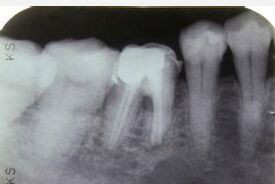

主诉:右下后牙咀嚼痛一月余。 病史:右下后牙冠部龋坏三月余,未治疗。现因咀嚼食物疼痛前来就诊

患牙拔除